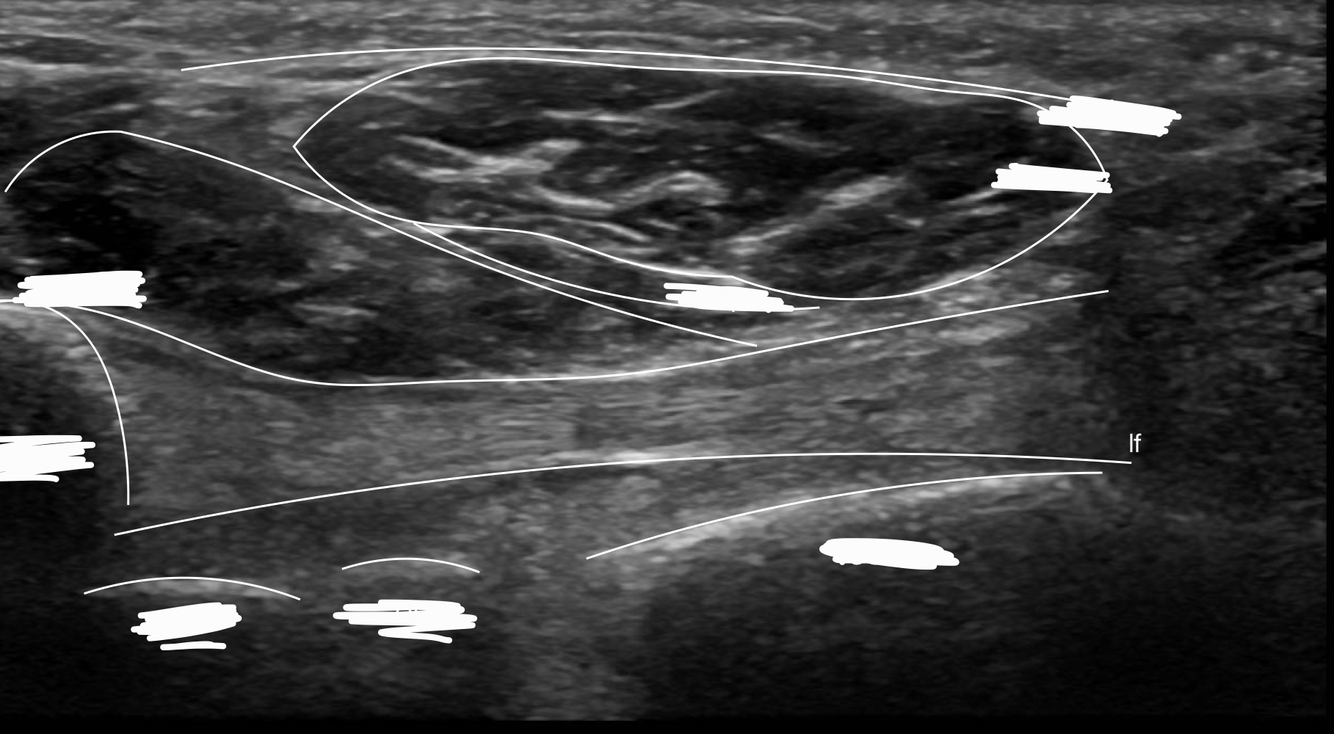

Q

Identifie le muscle long fibulaire sur l’image

Dans quelle structure ce muscle passe-t-il?